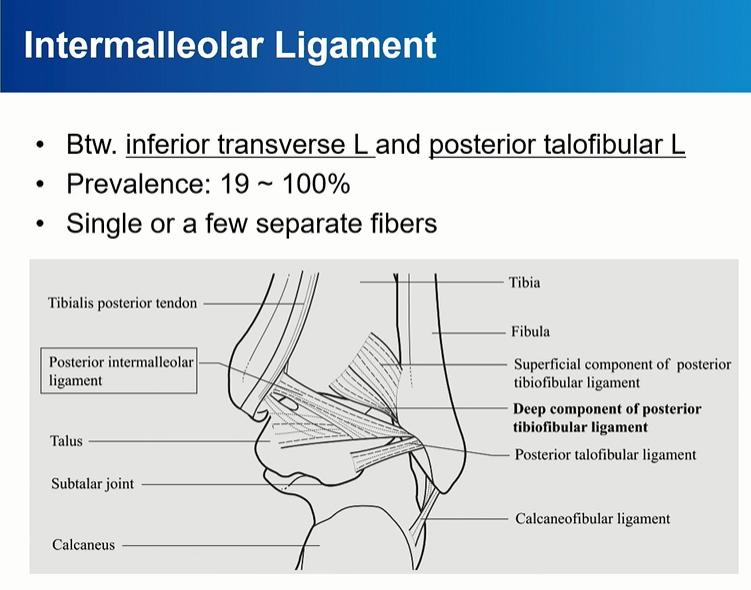

intermalleolar ligament는 PTFL 과 Deep PITFL (Inferior transverse ligament)사이에 존재.

비스듬한 주행, Lateral쪽으로 가면서 아래로 주행.